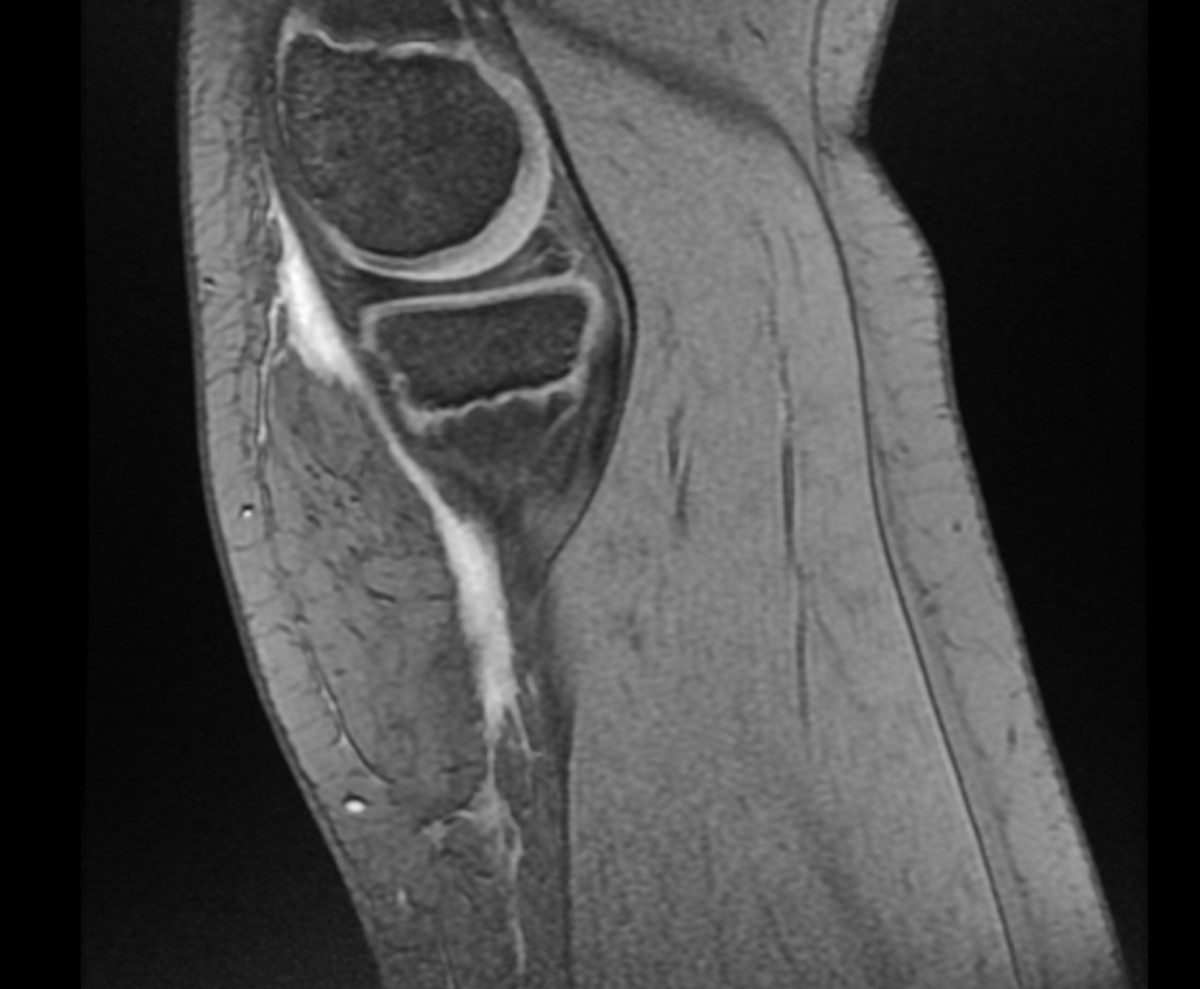

Fig. 2. RM secuencia T1: en el tejido celular subcutáneo profundo, adyacente a la fascia anteromedial de la rodilla derecha, se observa colección de 98 mm de eje longitudinal dentro de la cual se objetivan imágenes ovaladas con atenuación similar a la grasa en todas las secuencias (medidas 23 x 63 x 68 mm).